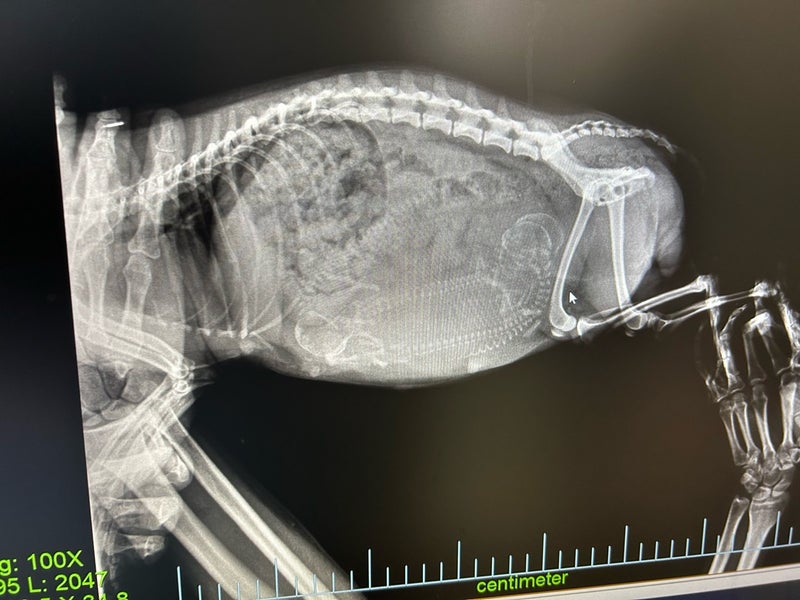

ひよりちゃんの出産が近くなってきましたので、今日は病院へ行ってレントゲンを撮ってもらいました

お腹には3ベビーが写っています

あと2、3日かな・・2日かな・・と先生